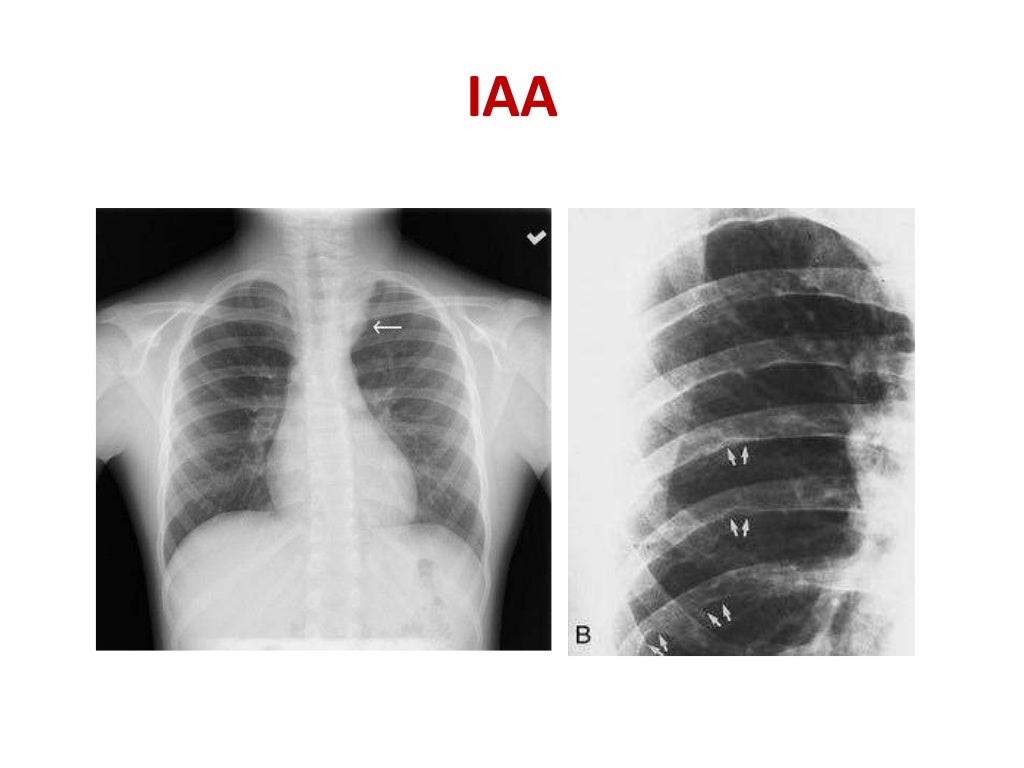

Rib notching Rib Notching Definition This article discusses how ribs are involved in a variety of traumatic, metabolic, inflammatory, neoplastic, and congenital disorders. Normal variants and abnormalities of the ribs are frequently encountered on chest radiographs. Acute rib infections are seen as focal areas of bone destruction, whereas chronic infections may manifest as periosteal reaction or a bone sequestrum. Rib notching are deformities that affect. Rib Notching Definition.

Rib notching Rib Notching Definition Normal variants and abnormalities of the ribs are frequently encountered on chest radiographs. This article discusses how ribs are involved in a variety of traumatic, metabolic, inflammatory, neoplastic, and congenital disorders. Rib notching are deformities that affect the upper surface of the rib, the lower surface of the rib (roesler’s sign), or both. Acute rib infections are seen as focal. Rib Notching Definition.